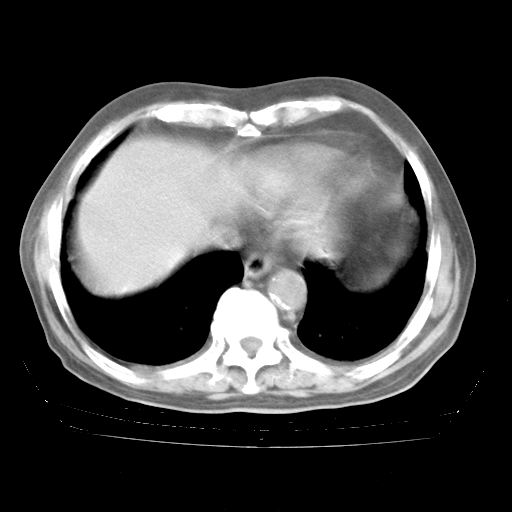

4月28日肺部CT——再次出现类似去年5月9日——透光度降低,“间质性”改变。

4月28日肺部CT——再次出现类似去年5月9日——磨玻璃样、间有“粟粒样”改变。

4月28日肺部CT

个人阅读4.14日肺部CT平扫:纵隔窗无异常,但肺窗示:双下肺内、后基底段有片絮状侵润影,部位以后基底段为著,以间质改变为主,呈急性肺泡炎征像,和首次住院影像学有相似之处。仅是个人读片,明日请相关专家再读片哈。其它建议同上。

1、108#的是4月14日的胸部CT(发此贴时还没看着28日的CT)。14日的胸部CT其实已经出现改变(如108#所述),个人认为28日的胸部CT除纵膈窗疑似有双侧胸膜增厚或少量胸积液(可行胸部B超明确)外,与4月14日对照病变有所加重;2、已经给予“异烟肼、利福平、乙胺丁醇”抗痨治疗?如果是,甲强龙80mg可缓慢减量;如果环磷酰胺已停用,暂不使用;3、中性粒细胞92%,明显升高,目前体温情况?注意合并细菌感染可能,使用左氧氟沙星情况下,是否联用B-内酰胺类抗菌药物?另外是查免疫全套非风湿全套。

今请临免主任会诊后认为:4月14日胸部CT已有双下肺间质性改变。患者病情复发多系激素减量过快不正规所致。目前甲强龙80mg/日,一周后酌情开始减量,不易过快。环磷酰胺若已停用,暂不使用。他同意目前抗菌药物使用,但应考虑是否加用B-内酰胺类抗菌药物(中性细胞明显增高);2、结核复发目前依据不足;3、若免疫全套各项指标正常,考虑多系特发性肺间质炎可能大。4、加强支持,并注意保护胃黏膜。

今上午去请教了临免、呼吸主任:1、介绍病史和阅读系列胸部CT一致认为:患者肺结核不考虑,仍为肺间质纤维化,目前处于急性肺泡炎阶段。2、若仍发热,可将甲强龙增至:80mg Bid静滴,同时鉴于中性增高,合并细菌感染可能,继续左氧氟沙星治疗,再联用B-内酰胺抗菌药物,如头孢哌酮--舒巴坦;3、停用抗痨药;4、目前甲强龙每日剂量160mg ,体温正常后再酌情减量;目前暂不用免疫抑制剂;4、不建议使用免疫增强剂等;5、加强支持治疗,鼓励患者进食;5、注意随访肝、肾功及血常规情况;6、因患者目前激素用量较大,加用胃黏膜保护剂,防止消化道出血可能。